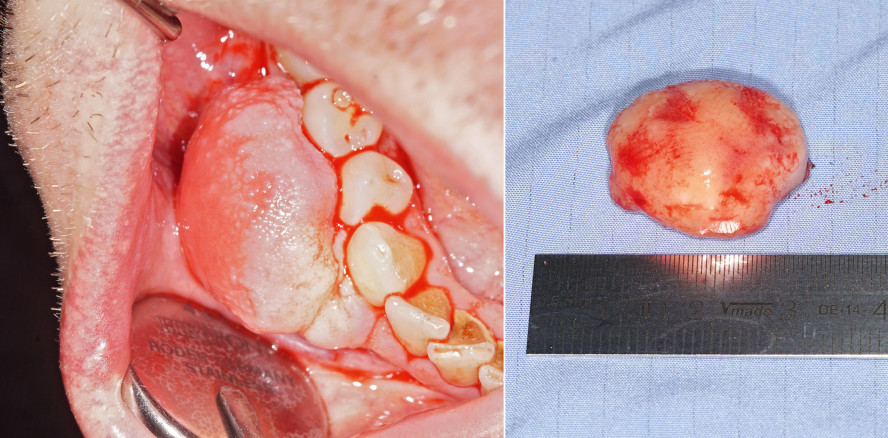

Im vorliegenden Fall wird eine Therapieoption zur Entfernung eines peripheren odontogenen Fibroms vorgestellt. In einem operativen Eingriff erfolgten die elektrochirurgische Exzision eines ausgedehnten Befundes sowie die Modellierung der Gingiva im Unterkiefer Regio 43–45. Durch diese Vorgehensweise konnten eine sichere und vollständige Entfernung des Fibroms sowie eine akzeptable ästhetische Rekonstruktion gewährleistet werden. Ein peripheres odontogenes Fibrom stellt eine absolute Rarität dar und soll in diesem Artikel im Rahmen einer Fallpräsentation näher beleuchtet werden.

Klinisch imponierte im rechten Unterkiefer in Regio 42–46 ein schmerzloser, 2 x 2 x 1 cm großer, polypös-prall-elastischer nach Regio 43/44 gestielt aufsitzender Lokalbefund. Beim vorsichtigen Abklappen des Tumors stellten sich die Zähne 43–45 unversehrt dar. Zur Ergänzung der Diagnostik wurde ein Orthopantomogramm erstellt. Es zeigten sich im Ober- und Unterkiefer metalldichte Verschattungen im Sinne von konservierenden Füllungen im Bereich der Molaren des linken und rechten Ober- und Unterkiefers sowie im rechten Frontzahnbereich des rechten Oberkiefers. In der Röntgenaufnahme konnten keine periapikalen oder intraossären Läsionen nachgewiesen werden. Insbesondere die Regio 42–46 zeigte sich unauffällig.

Nach Schmerzausschaltung durch Lokalanästhesie mit Ultracain® D-S forte (Adrenalin 1:100.000) erfolgte die elektrochirurgische Exzision des Tumors und die ebenso elektrochirurgisch durchgeführte Modellation der marginalen Gingiva in Regio 43/44. Auf einen Zahnfleischverband wurde verzichtet.

Der histologische Befund zeigte eine vorgewölbte, leicht verdickte Schicht verhornenden Plattenepithels. Intra- und subepithelial zeigten sich lockere gemischtzellige entzündliche Infiltrate. Weiterhin konnten eine myxoide Auflockerung, pseudozystische Areale und wechselnde Lymphangiektasien nachgewiesen werden. In einer weiteren Aufbereitung des Materials konnten im Rahmen der Alcianblau-Reaktion mukoide Verquellungen dargestellt werden. Zudem zeigten sich Epithelnester (Malassez‘sche Epithelnester).

Makroskopisch präsentiert es sich weiß, solide und zeigt nur eine sehr geringe Infiltrationstendenz. Histologisch können nach der aktuellen WHO-Klassifikation zwei unterschiedliche Typen des odontogenen Fibroms unterschieden werden (Tab. 1).